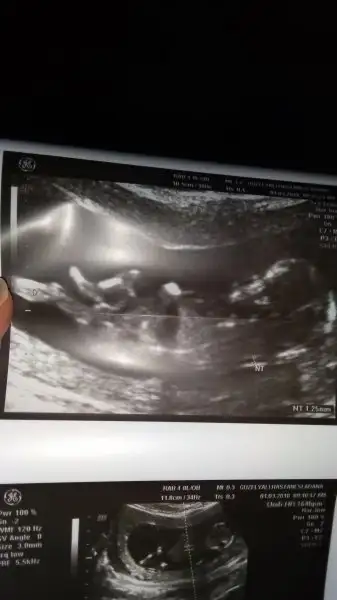

Az once attim ama resim gozukmuyodu ondan tekrar attim yorumlarsaniz sevinirim :)

• 20180316_144508-1.webp

20180316_144508-1.webp

12 KB · Görüntüleme: 90